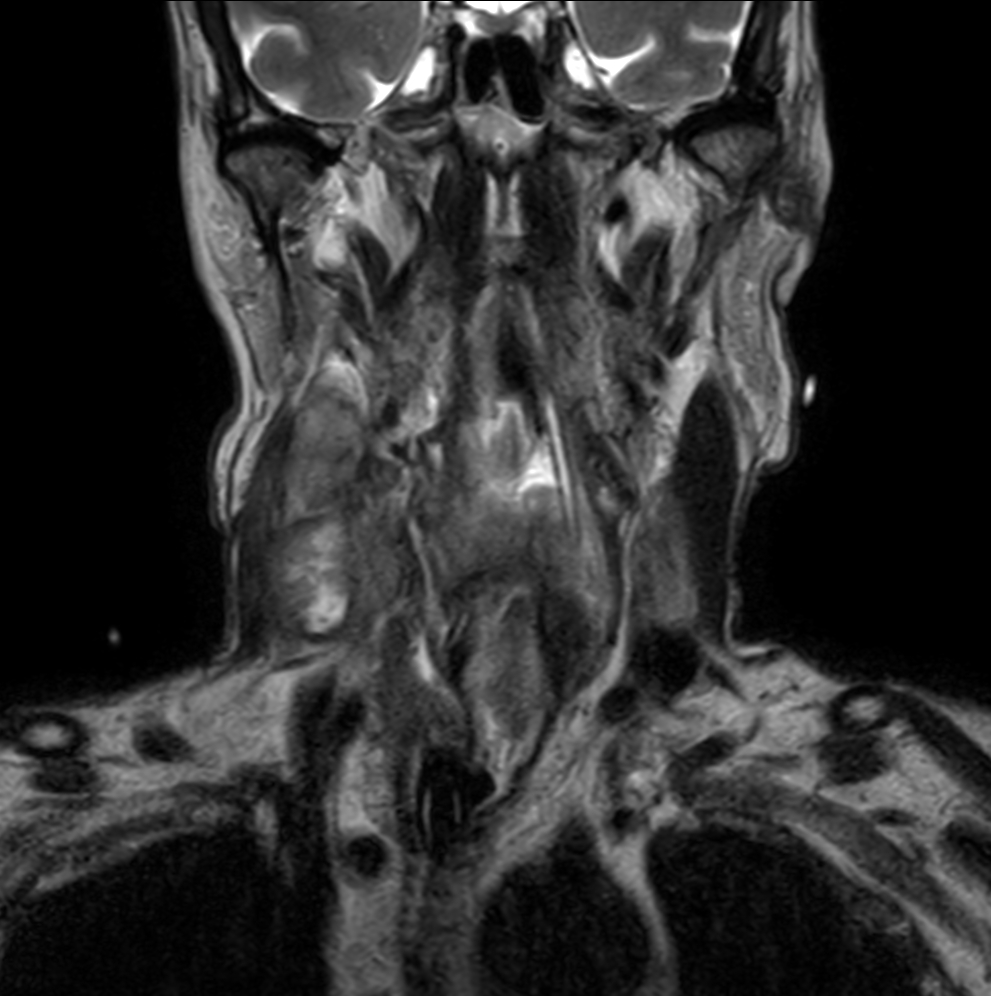

Coronal T2w TSE